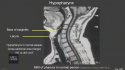

Chauvin’s defense lawyers are suggesting that drugs ― and not the 9 minutes and 29 seconds that Chauvin pressed his knee against Floyd’s neck ― caused Floyd’s death in May 2020.

“The experts will opine during this case that the average human being can go without oxygen from 30 seconds to 90 seconds — where George Floyd went without oxygen for over 429 seconds, and that’s why it was intentional what this officer did,” Crump added.